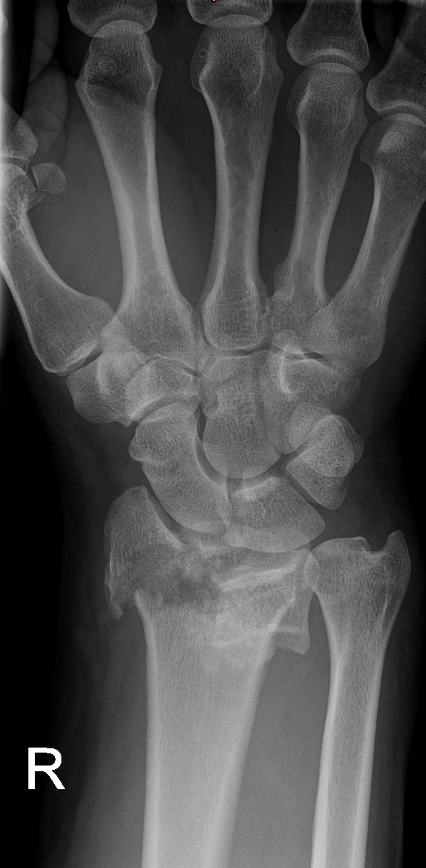

High-energy distal radius fractures are characterized by significant displacement of bone fragments, articular surface damage, and ligamentous injury. Tendon interposition between bone fragments occurs very rarely. In this report, we present a case of a complex distal radius fracture in which intraoperative findings revealed interposition of the flexor digitorum superficialis tendon of the index finger beneath one of the fracture fragments. The exceptional rarity of this situation prompted the authors to report this case.